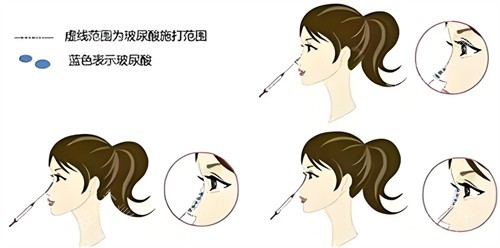

个性化美学设计

提供多种鼻型方案,根据个人面部比例进行定制。重视与整体整体风格的协调,避免千篇一律,实现自然协调的外观。